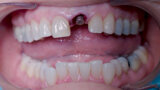

Fig. 2: Initial situation, intra-oral view.